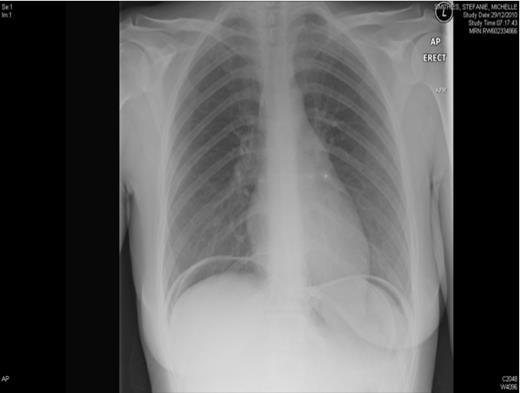

She was seen by Surgeons who advised for an erect chest x-ray which showed gas under the diaphragm implying the diagnosis of perforated peptic ulcer disease. Her past medical history was unremarkable. She had undergone abdominal hysterectomy three months before for menorragia. Her post operative review was uneventful and vault has healed well.